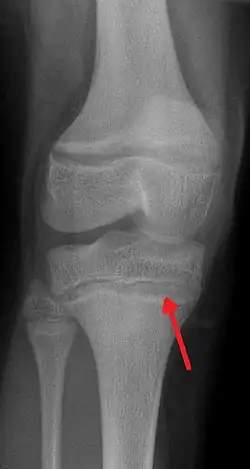

![]() Рентгенография. Характерное изменение метафиза при отравлении свинцом. | |